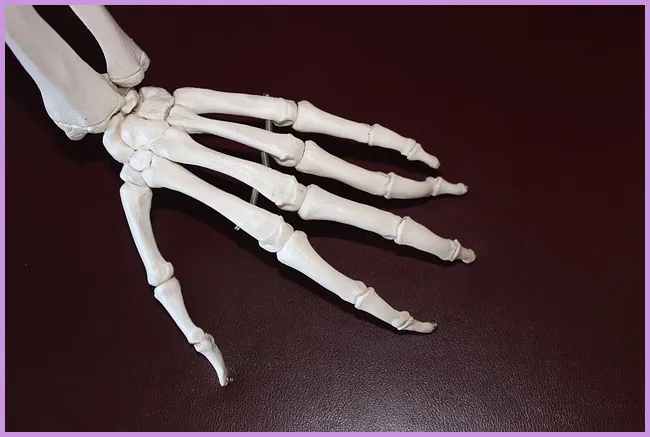

손가락 관절염의 이해

손가락 관절염은 일반적으로 두 가지 종류로 나뉩니다: 퇴행성 관절염과 류마티스 관절염입니다. 퇴행성 관절염은 나이가 들면서 발생하는 자연스러운 변화로 인해 관절의 연골이 마모되면서 통증과 염증을 초래합니다. 반면, 류마티스 관절염은 면역 체계의 이상으로 발생하는 자가면역 질환입니다. 이 두 가지 유형의 관절염은 치료법과 관리 방법이 다르기 때문에 정확한 진단이 중요합니다.

손가락 관절염은 많은 사람들이 겪는 고통스러운 질환입니다. 이 블로그 포스팅에서는 손가락 관절염의 치료법, 다양한 종류의 관절염 약, 그리고 퇴행성 관절염의 이해를 돕기 위해 깊이 있는 정보를 제공해 드리겠습니다. 손가락 관절염은 손가락의 관절에 염증이 생겨 통증을 유발하며, 일상생활에 많은 불편함을 초래합니다. 이에 대한 적절한 치료와 예방 방법을 같이 살펴보면 좋겠습니다.